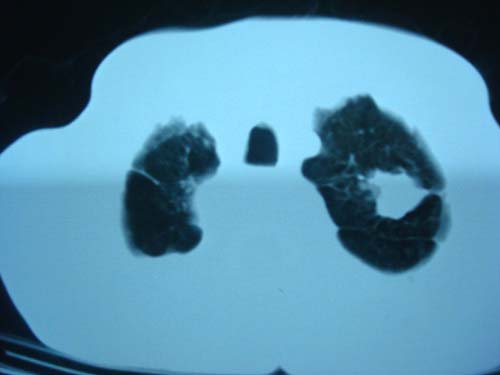

男性,45岁,胸疼,低热,抗炎治疗后症状缓解拍片检查发现左上肺有高密度灶,考虑结核,做ct示条件有限采集了部分图像,图像质量差请谅解

考虑两肺上叶继发性肺结核;肺气肿(多发肺大泡)。

考虑两肺上叶继发性肺结核;肺气肿(多发肺大泡)。建议:追踪复查

考虑双肺上叶继发性肺结核,定期复查。